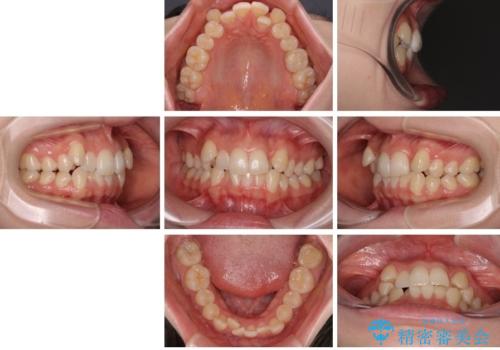

八重歯が気になる。補助装置を併用したワイヤー矯正

- 20代女性

- 治療期間

- 2年

- 八重歯が気になるとのことで来院された患者様です。

上顎前歯部はデコボコが強く、歯を並べるためのスペースが不足しているため、左右の第一小臼歯を抜歯することとしました。

また、抜歯して確保したスペースが不足してしまうのを防ぐため、補助装置を併用しています。

矯正治療の前に上下左右の親知らずの抜歯も行いました。

補助装置を併用したおかげで、出っ歯になることなくスムーズに治療を終えることができました。